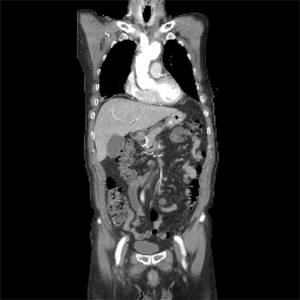

복부 대동맥류

술전 CT 및 복부대동맥 내 스텐트 삽입술 후 CT

술전 CT

복부대동맥 내 스텐트 삽입술 후 CT